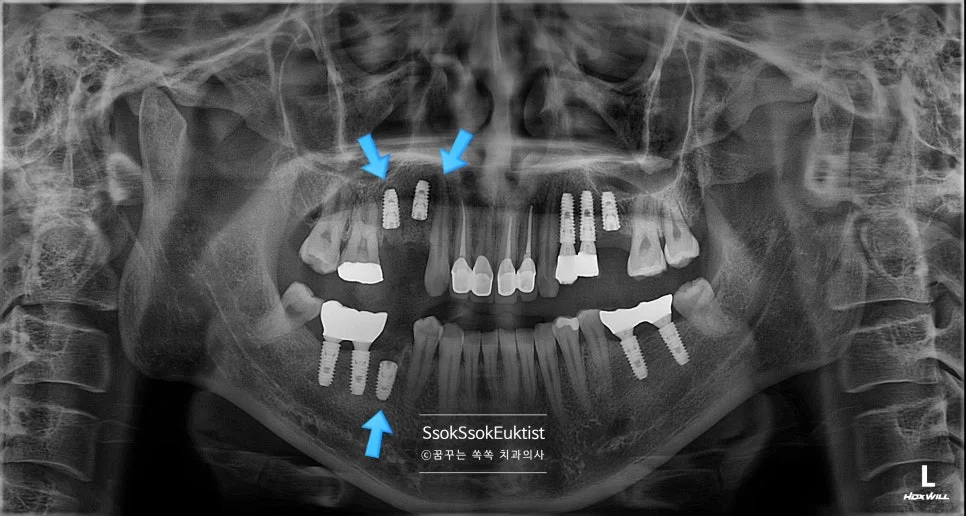

CBCT 파노라마 진단 영상 — 1~4번 치아 위치의 문제점 화살표 표시

사진에서 1번, 4번 치아의 경우 치아 머리가 너무 남지 않아 발치 후 임플란트가 필요한 상황입니다.

1번, 4번 치아의 경우 자연치아 살리기 조건 중 세 번째 조건을 만족하지 못하여 발치의 대상입니다.

한편, 3번의 경우 치아를 발치하고 오랜 시간이 지난 위치로 예쁘게 임플란트 식립을 진행하면 됩니다.

그런데 2번의 임플란트를 한번 보면 뭔가 잇몸이 부자연스러운 것을 볼 수 있는데요.

임플란트 주변에 뼈가 다 녹아내리고 그 바깥에 잇몸까지 혈류를 받지 못해 점점 괴사하고 있는 모양새입니다.

CBCT 단면 영상 — 임플란트를 감싸고 있어야 할 뼈가 다 녹아 없어진 모습

임플란트가 뼈와 유착에 성공은 하였다 하더라도 임플란트를 감싸고 있는 뼈가 부족하면 이렇게 점점 임플란트 주위염으로 뼈와 잇몸이 녹아내리게 되는데요.

이래서 임플란트는 가급적 깊게 그리고 입천장(혀) 쪽으로 위치하여 식립하여야 합니다.

이 임플란트는 점점 염증이 심해질 것이고 그나마 남아 있는 잇몸까지 녹게 되면 이후의 치료가 너무 어려워지기에 임플란트를 제거한 후 재식립을 시도합니다.